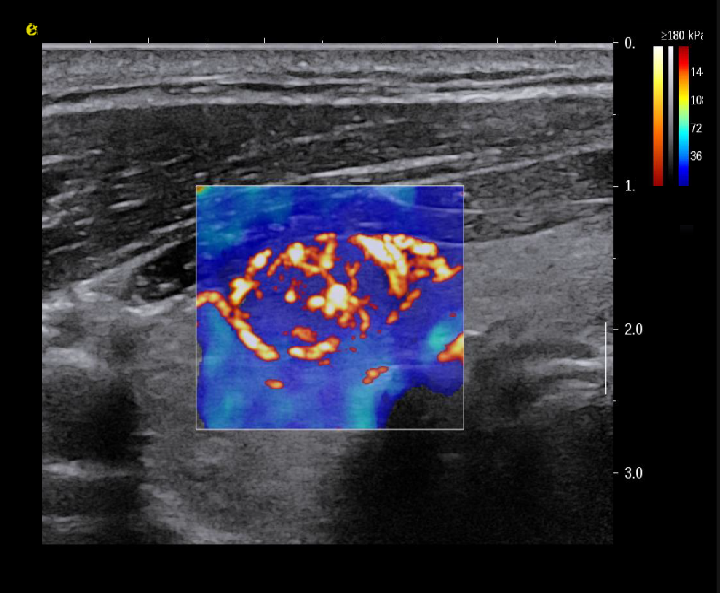

多模态复合成像

image.png与传统单一成像模式相比,多模态复合成像技术能在同一幅图像中同时呈现二维组织信息、组织血管结构及其分布,以及组织硬度信息。这种成像方式使医生能够更直观地观察病变组织的解剖结构、血液供应和硬度状况,从而为临床治疗方案的制定提供更具体、形象的参考。

image.png